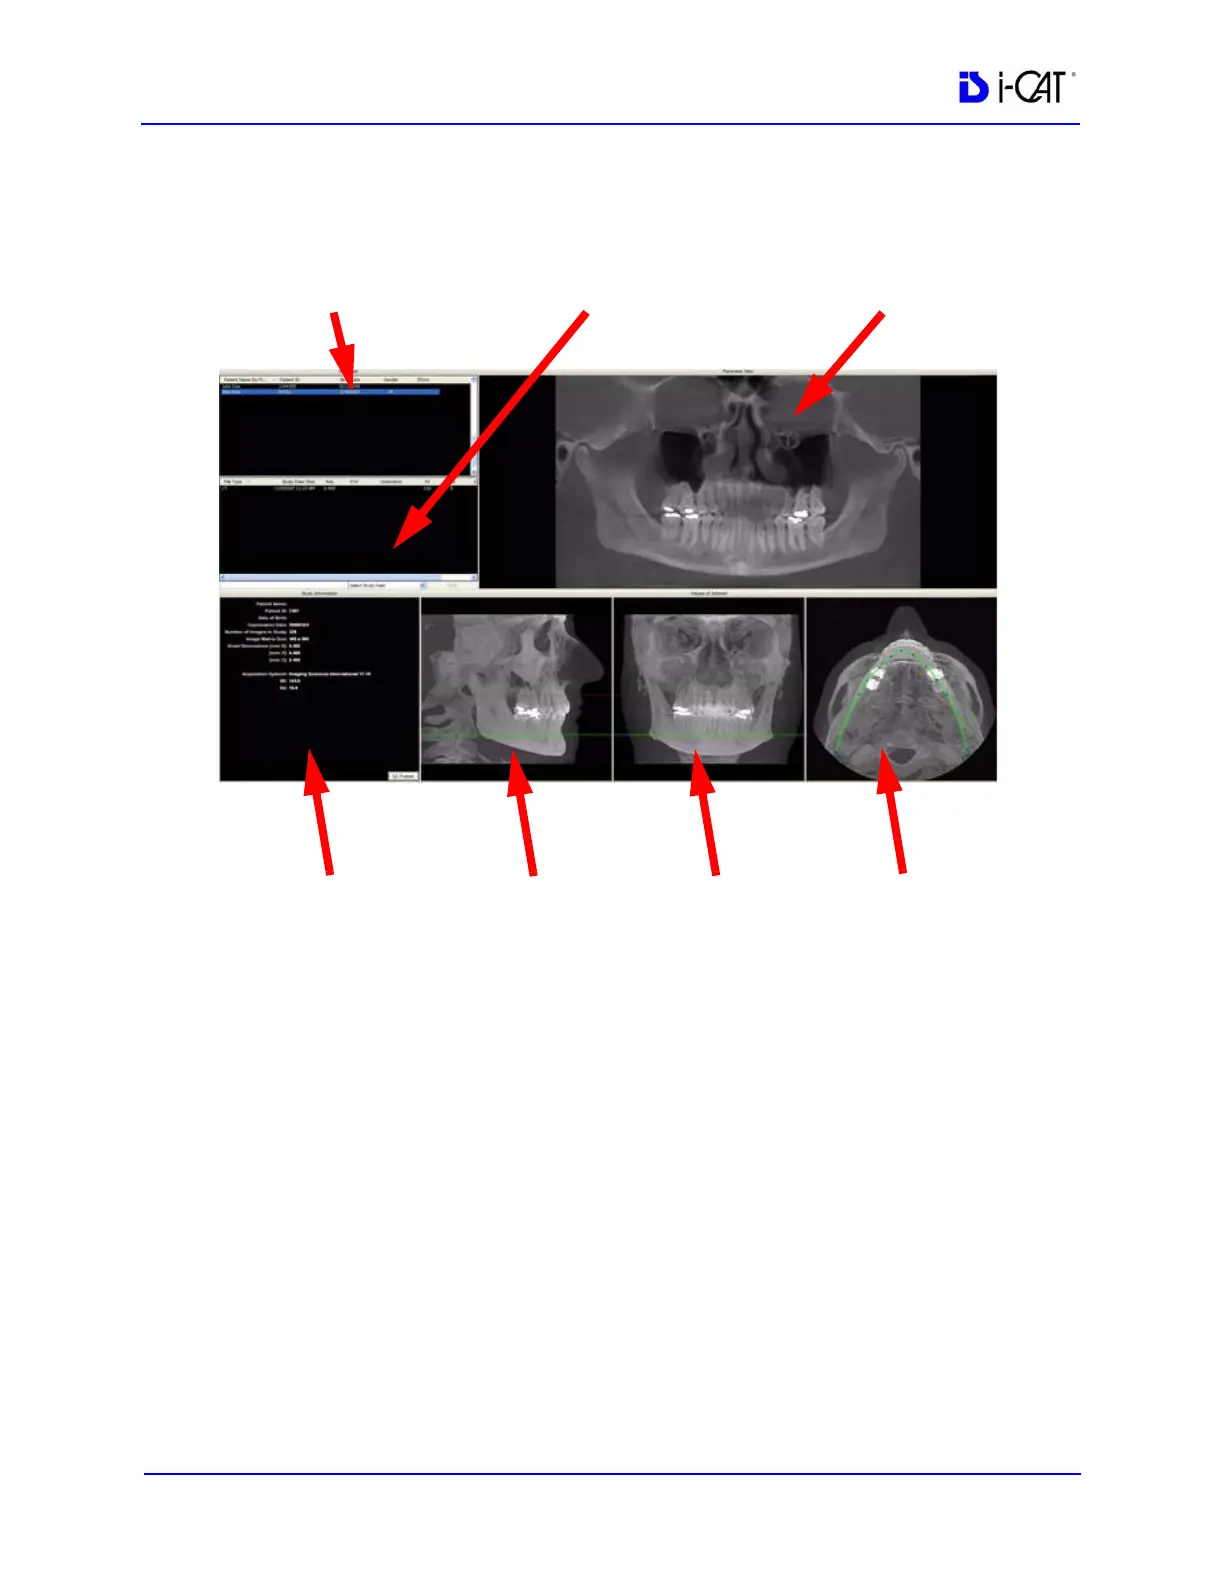

Once data is successfully reconstructed, the Preview screen appears

as shown below, showing the Panoramic, Sagittal, Coronal, and

Axial views of the skull through midline.

The Preview Screen is divided into seven views:

Patients in Database

Patient Images

Patient Detail View

Panoramic View

Sagittal View

Coronal View

Axial View

Patients in Database lists all Patients and their data who are entered

into the database.

Patient Images lists all images that pertain to the selected

(highlighted) Patient from the Patients in Database list.

PATIENT DETAIL

VIEW

SAGITTAL

CORONAL

AXIAL

PATIENT DATABASE PATIENT IMAGES PANORAMIC VIEW